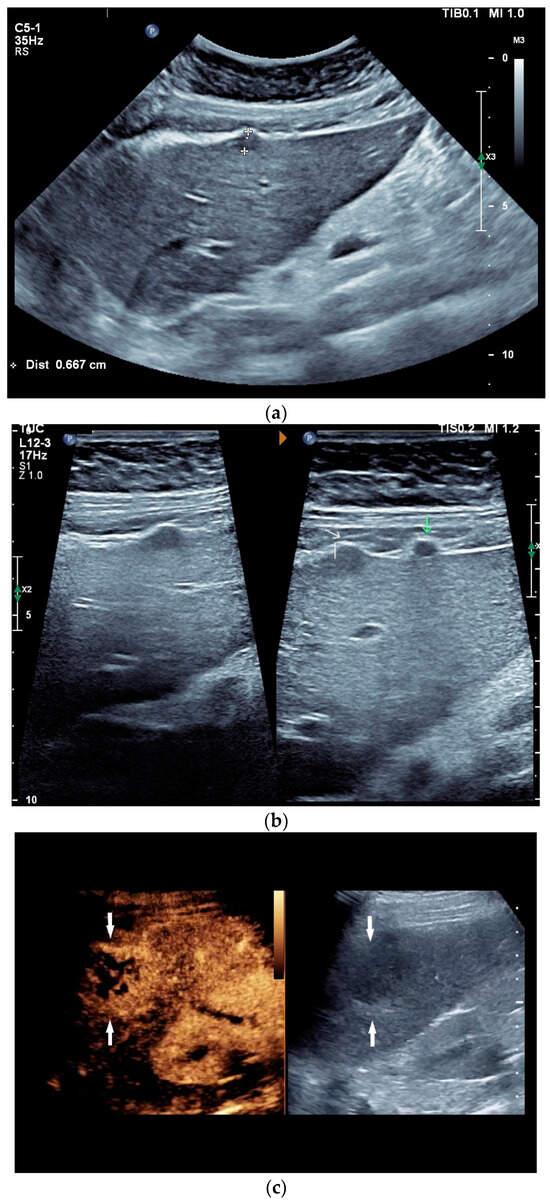

Figure 2.

A case of extrapulmonary tuberculosis: 33 y/o male from a country at high risk of tuberculosis. Thoracic pain and fever led to a suspicion of pericarditis. There was no pericardial effusion. There were no pulmonary infiltrations or pleural effusions in the chest CT, but there were enlarged mediastinal lymph nodes. Ultrasound and CT also showed subdiaphragmal enlarged lymph nodes and small nodular splenic changes. The diagnosis was confirmed using the transgastric EUS-guided biopsy (19 G Olympus) of the lymph nodes in the hepatic hilum. Enlarged lymph nodes in the hepatic hilum (a); adjacent to the pancreatic head (b); transabdominal ultrasound (TUS) using a linear transducer of 9 MHz. The hypoechoic central parts are conspicuous (a,b). Rounded lymph nodes are observed as being peripancreatic (c) and as being in close proximity to the gallbladder wall (d). The lymph nodes are visualized between the markers. In the EUS, paragastric lymph nodes are enlarged, rounded, very hypoechoic, with hypoechoic central parts, and forming conglomerates. A central vascular hilum cannot be delineated in the CDI (e). The hypoechoic central parts are softer during elastography (f). EUS also shows enlarged hypoechoic lymph nodes in the hepatic hilus, with hypoechoic central parts that lack a central vascular hilum (g). Elastographically, the lymph nodes are indifferent (h). The diagnosis is confirmed using EUS-guided biopsy (i) with evidence of granulomatous inflammation, caseous necrosis, detection of acid-fast rods, and Mycobacterium tuberculosis in the PCR. In the spleen, single hypoechoic lesions < 5 mm are visible during transabdominal ultrasound using a linear transducer of 9 MHz. Otherwise, fine-grained hypoechoic lesions can only be guessed at (j). With magnification using a 9 MHz transducer, multiple hypoechoic lesions < 3 mm can be delineated (k). These do not reveal any vessels in the Power Doppler (l). EUS confirms multiple hypoechoic splenic lesions, in line with splenic tuberculosis (m).